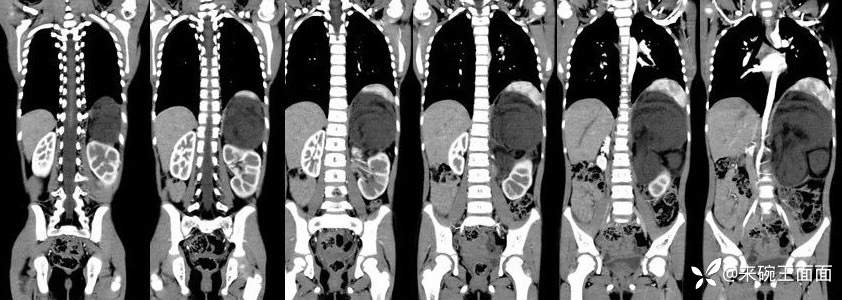

[现病史]1月余前无明显诱因发现左上腹肿物,无发热,无呕吐,无腹痛、腹泻、排便困难及其他不适,无尿频尿急,至当地医院CT示左上腹巨大占位性病变。【体格检查]腹膨隆,未及胃肠型及蠕动波,未及腹壁静脉曲张,腹软,左上腹可及大小约10*10cm肿物,质中,位置固定,无压痛、反跳痛,肝脾肋下未及,移动性浊音阴性,肠鸣音4-5次/分。

左上腹巨大软组织肿块影,密度混杂,边界清楚,其内可见脂肪密度,增强扫描未见强化。